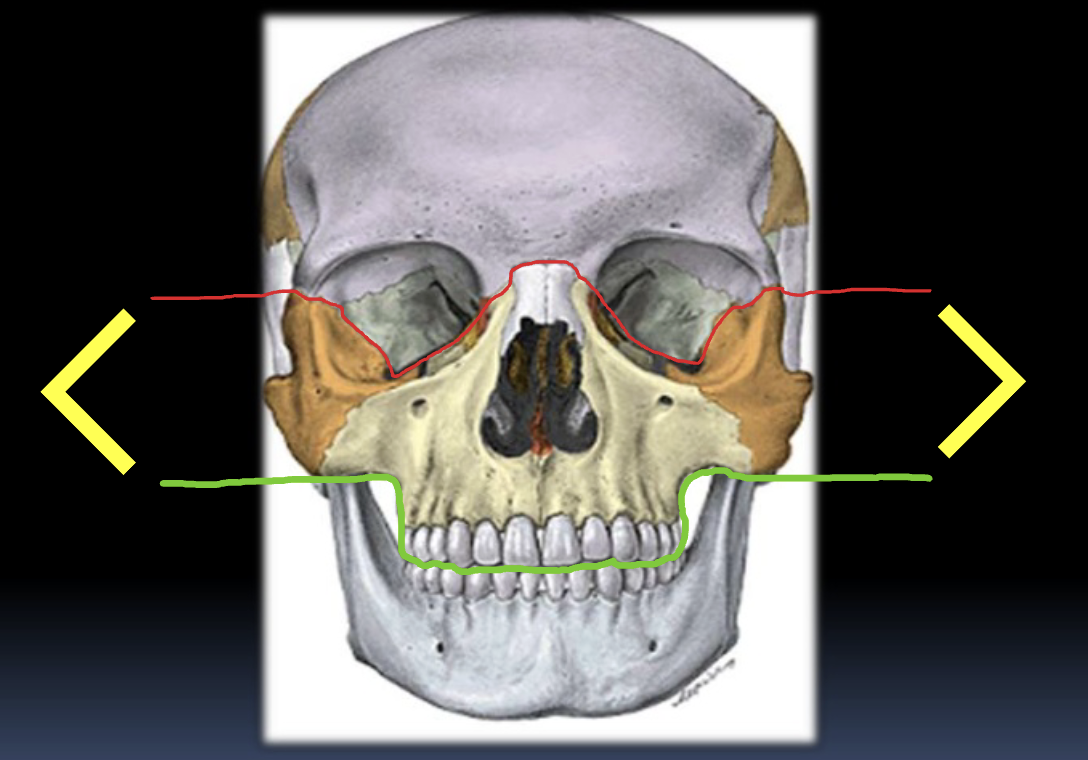

Q

¿Qué importancia tiene la espina nasal en TC?

A

Tiene forma de “Y” y sirve como base donde reposa el cartílago del septum nasal